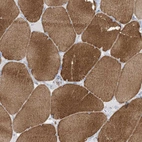

Immunohistochemical staining of human skeletal muscle shows moderate to strong cytoplasmic positivity in myocytes.